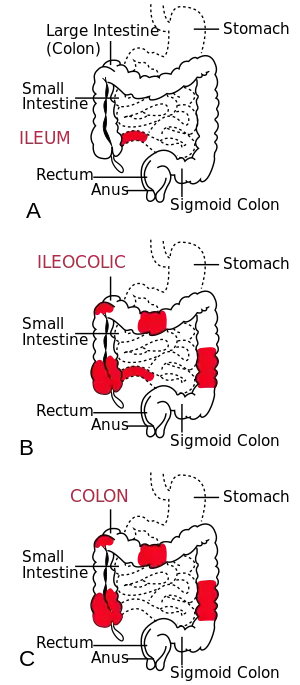

| The three most common sites of intestinal involvement in Crohn's disease | |

Crohn's disease is one type of inflammatory bowel disease (IBD). It typically manifests in the gastrointestinal tract and can be categorized by the specific tract region affected. A disease of both the ileum (the last part of the small intestine that connects to the large intestine), and the large intestine, Ileocolic Crohn's accounts for fifty percent of cases. Crohn's ileitis, manifest in the ileum only, accounts for thirty percent of cases, while Crohn's colitis, of the large intestine, accounts for the remaining twenty percent of cases and may be particularly difficult to distinguish from ulcerative colitis.

Gastroduodenal Crohn's disease causes inflammation in the stomach and first part of the small intestine called the duodenum. Jejunoileitis causes spotty patches of inflammation in the top half of the small intestine, called the jejunum.[131] The disease can attack any part of the digestive tract, from mouth to anus. However, individuals affected by the disease rarely fall outside these three classifications, with presentations in other areas.[1]